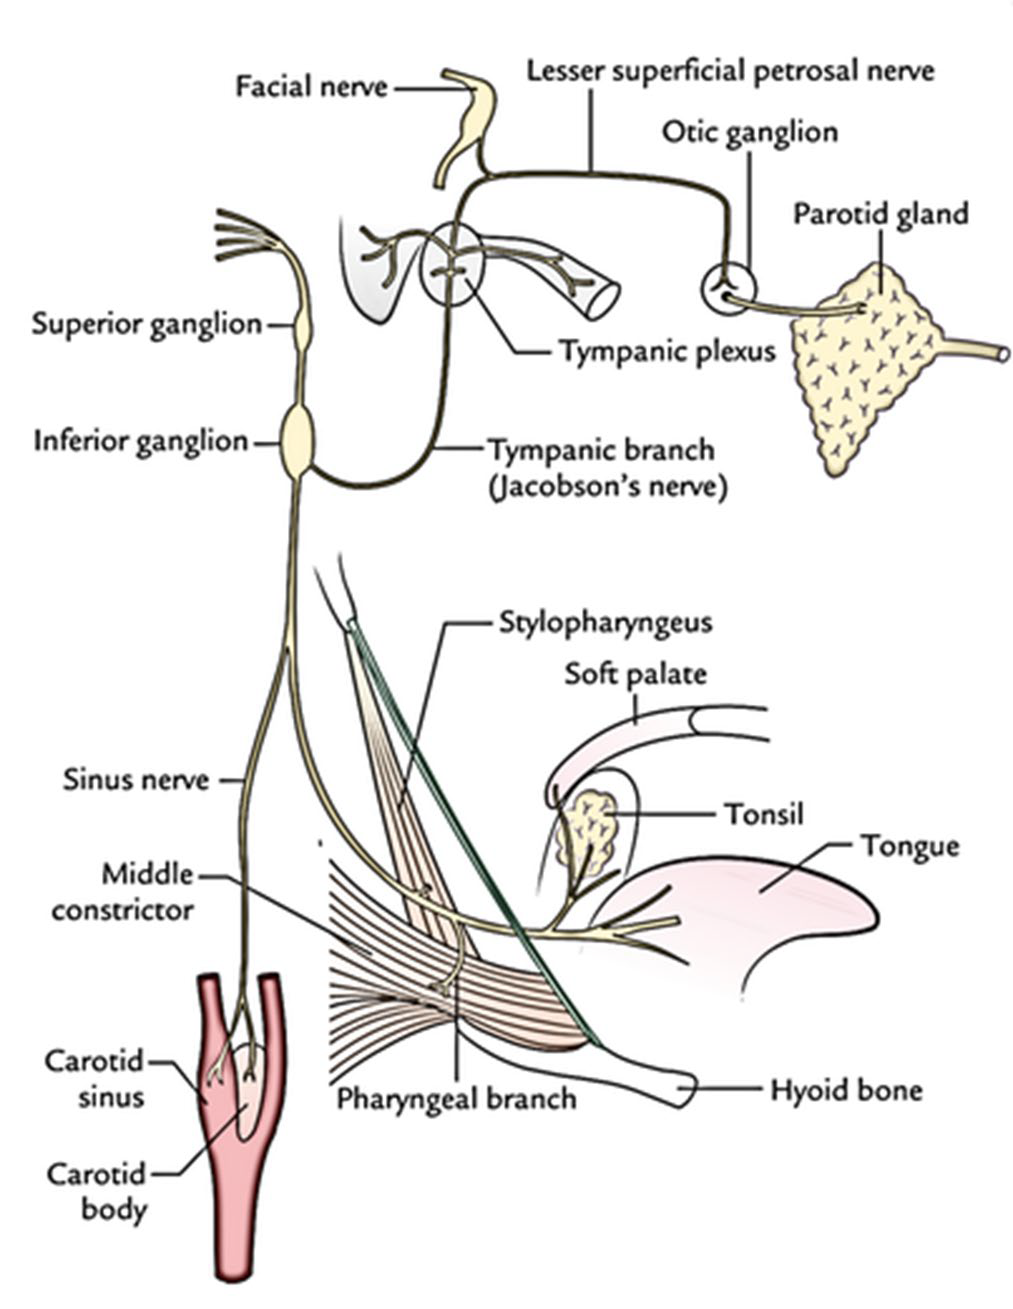

CN IX

Motor

- Stylopharyngeus m.

- Lesser petrosal n.(Parasymphysis)

- 支配Parotid g.的副交感節前神經

Sensor

- Tympanic n.

- 中耳、鼓膜內面、耳咽管(Eustachian)

- Sinus n.

Terminal

- Pharyngeal br.(with CN X)

- Mucosa of oropharynx

- Tonsillar br.

- Palatine tonsil

- Lingual br.

- 舌頭後1/3味覺、一般感覺